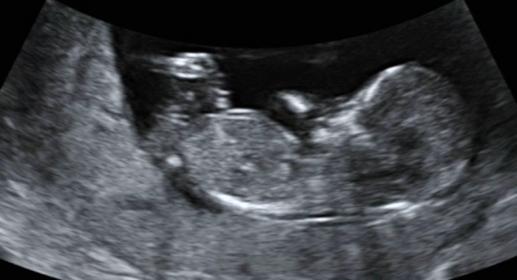

Here are some photos from my 12w ultrasound...I have a son and am hoping for a girl. Opinions, pretty please? I am dying to know!

Attachment 16294

Looks girly! :)

I guess boy due to the blob on top. Sorry that isn't what you are hoping to hear!!

I think maybe girl.....

Girl! What did the dr say?

I am going with boy.

I'm thinking boy too, hope I'm wrong tho and you get your girl

I am leaning girl.

I don't really know how to read these things but just looking at yours if I had to guess i'd say girl.

my guess is girl!

Thanks everyone, 6 girl and 3 boy guesses...it will be interesting to see what it is. I'll update you when I know (end of February) :)

UPDATE: we found out today that we are having a girl!!!! Thanks for all your predictions, very excited!